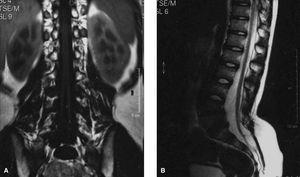

Con el diagnóstico clínico de hipertricosis localizada lumbosacra o cola de fauno y ante el alto índice de sospecha de la existencia de un disrafismo espinal oculto, se solicitó una resonancia magnética de la columna vertebral. Esta prueba de imagen puso de manifiesto la presencia de 2 vértebras (L4-L5) con morfología en mariposa (fig. 2), mostrando a nivel posterior un espolón óseo que divide el canal raquídeo en dos. Están ausentes las apófisis espinosas de dichas vértebras lumbares y de las sacras y a nivel de L3 la médula espinal se divide en 2 hemimédulas (fig. 3A). Estos hallazgos permitieron confirmar la presencia de un disrafismo oculto, compatible con una diastematomielia, apreciando una médula espinal anclada (fig. 3B).

Figura 3. A) RM: detalle de las división medular en dos hemimédulas a nivel de L3.B)RM: detalle de la médula anclada a dicho nivel.